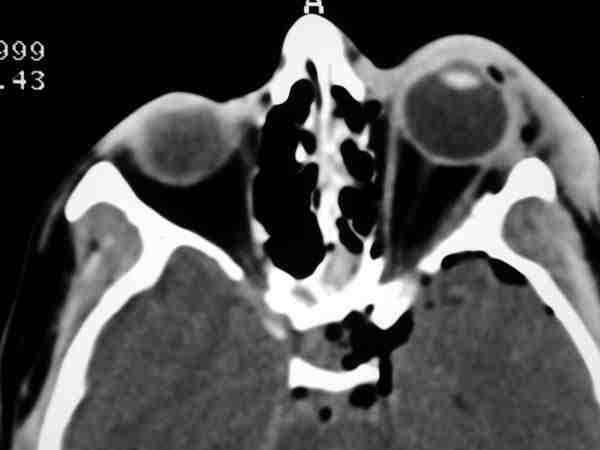

58-03.jpg (8530 bytes)

Figura 3. Imagen de TC , en proyección axial, que muestra la compresión de los elementos del ápex orbitario en un paciente con displasia fibrosa.

El tratamiento está condicionado por la severidad de la lesión, reflejado en la pérdida de agudeza visual, debiendo realizarse una descompresión del nervio óptico mediante un abordaje transcraneal (5,6). No se recomienda la radioterapia, ya que puede inducir una transformación sarcomatosa.